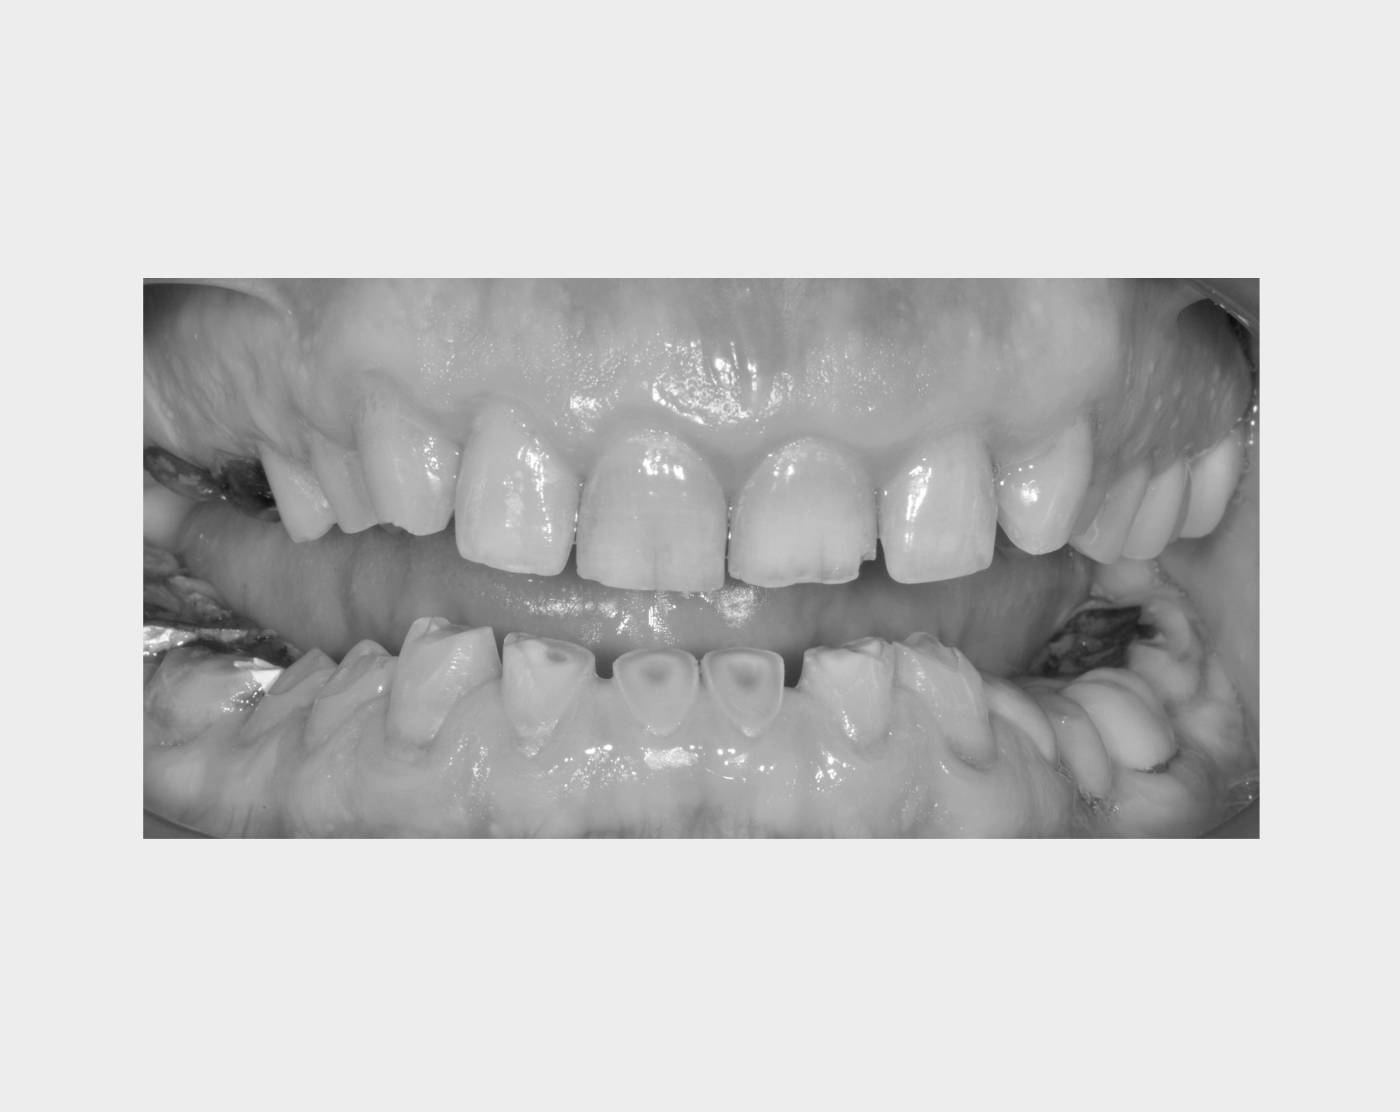

Il bruxismo, cioè il digrignamento involontario dei denti, può provocare mal di testa, dolori mandibolari e usura dentale se non trattato. Nel nostro studio valutiamo ogni caso e proponiamo interventi su misura, come il bite notturno personalizzato, studiato per proteggere i denti e migliorare il comfort durante il sonno. Grazie a questo approccio, è possibile ridurre il rischio di danni dentali e alleviare i sintomi legati al bruxismo.